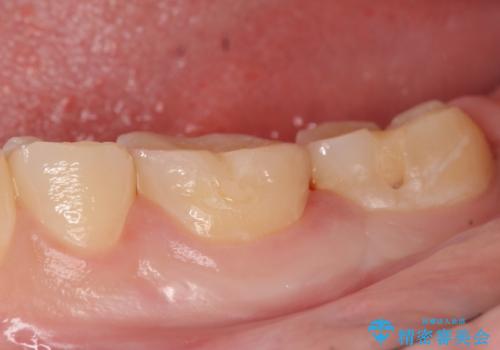

検査の結果左下6が虫歯になっていたため、セラミックインレーによる修復を行いました。

- セラミックインレー…¥70,000費用は治療当時の料金となります

当院のセラミックインレーはemaxという強度と審美性に優れた材料を使用しています。

またプレス方式でインレーを製作しているため、削り出しで製作するCADCAMより優れた適合性も持ち合わせており、虫歯が再発しにくい修復物です。